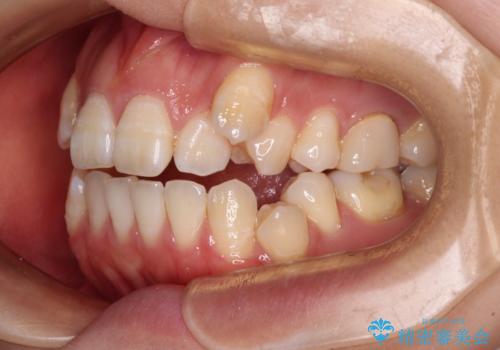

- 咬み合わない前歯と八重歯などのデコボコを気にして来院された患者様です。

上下前歯の位置を比較すると上顎が前方にあり、デコボコ改善でより上顎が前方に行く可能性があります。

開咬の改善にはインビザラインが有効であり、インビザライン単体での治療を検討しましたが、上顎前突を回避するために上顎左側第一小臼歯抜歯を行うこととしたため、補助装置とワイヤー矯正を併用した上で、インビザラインによる矯正治療を行うこととしました。